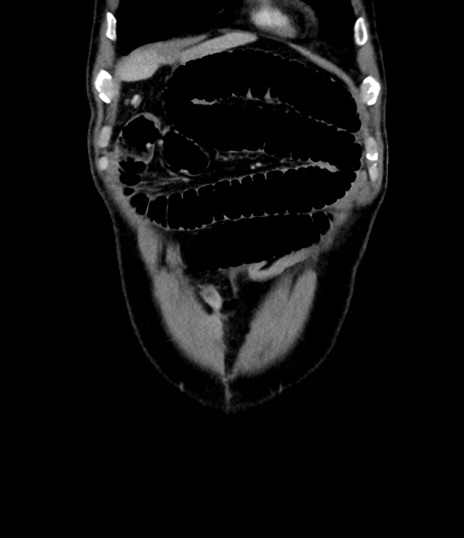

横断像

【症例】 60歳代男性

【主訴】 黒色吐物

【現病歴】 4日前から嘔気自覚、2日前の朝食後にも嘔気あり、自分で手で嘔吐反射起こし嘔吐したところ血が混ざっていたため受診。

【既往歴】 5年前汎発性腹膜炎を伴う急性虫垂炎で手術、高血圧、前立腺肥大症、高脂血症

【身体所見】 腹部正中に手術癩痕あり 腹部平坦・軟圧痛なし膨満感あり

【データ】WBC 8400、CRP 4.54